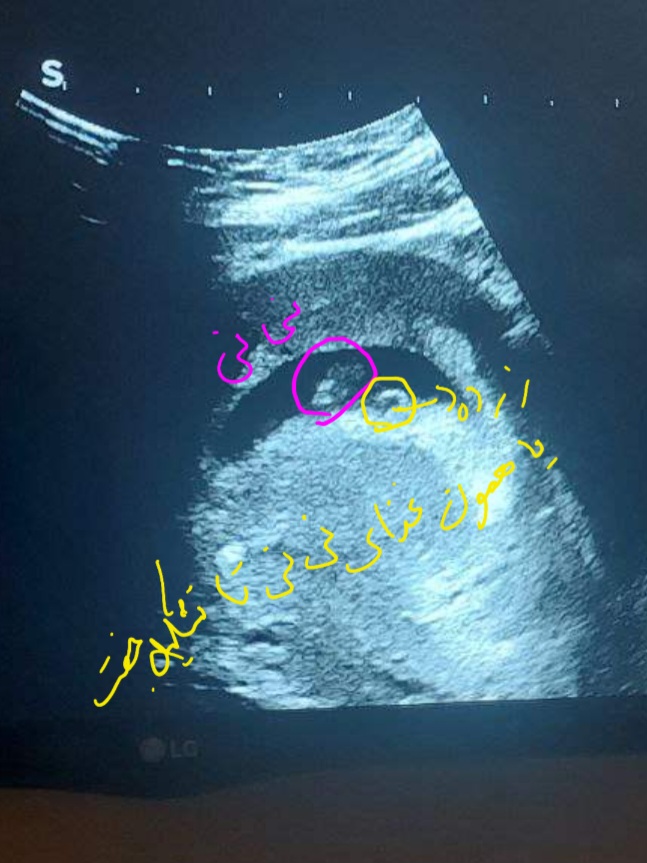

اونی که شکل هلال ماه کیسه آبه، اون دوتا چیز سفید وسطش گرده کیسه زرده ، جنین شکل c

همون c کوچولو جوجه شماس😍